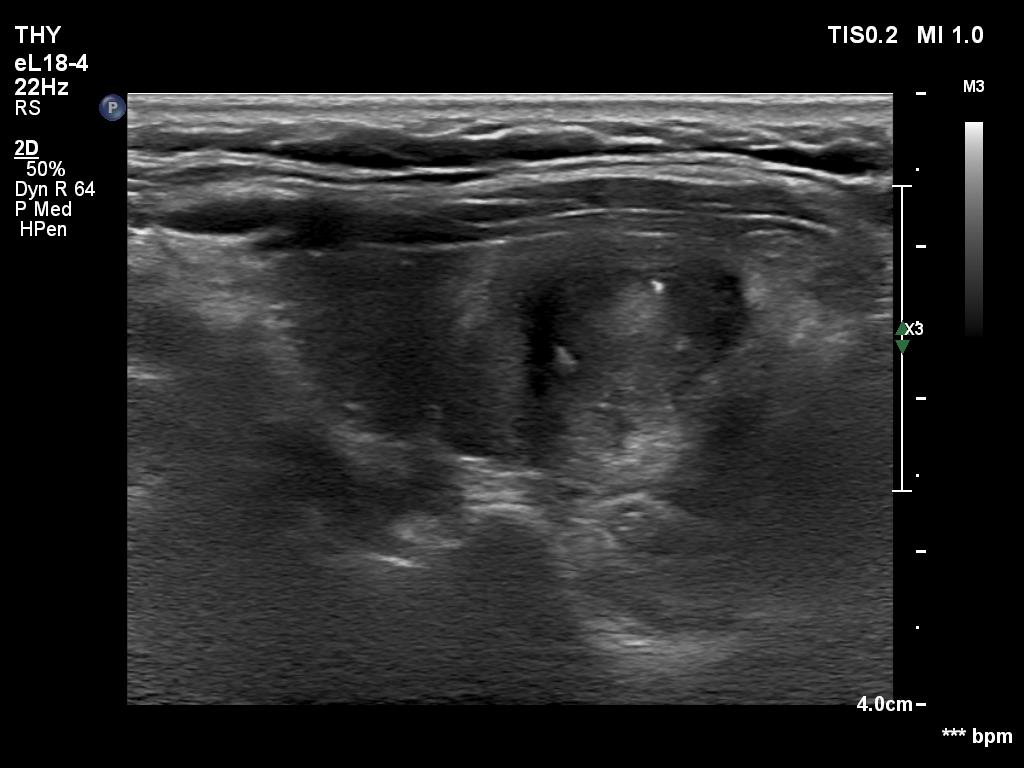

TIRADS - case 294 (ultrasonographic picture 7)

Left lobe, longitudinal scan with better harmonization. The bright echogenic granule seems to have a tail and is located ventral to a tiny cystic area.